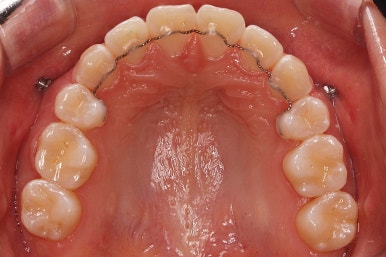

아래턱이 작아서 상대적으로 윗니들이 많이 돌출되었고, 뻐드러져 있습니다. 윗니들이 배열되어 있는 형태도 V자에 가깝게 입천장이 좁은 양상입니다.

윗니는 발치를 했고, 잇몸뼈에 미니스크류를 식립하여 앞니를 뒤로 당겨넣고 있습니다.

틈은 다 다물어졌고, 부가적인 정교한 마무리 과정을 더 거치게 됩니다.

중앙선도 잘 맞고 교합도 잘 마무리되었습니다.

이 뽑은 자리가 다시 벌어지지 않게 앞니가 다시 틀어지지 않게 유지철사를 부착하고 마무리를 하였습니다.

중앙선, 교합, 뻐드러짐 모두 좋아졌고 이를 뽑고 교정했지만 발치 공간이 남지 않고 잘 마무리 되었습니다.